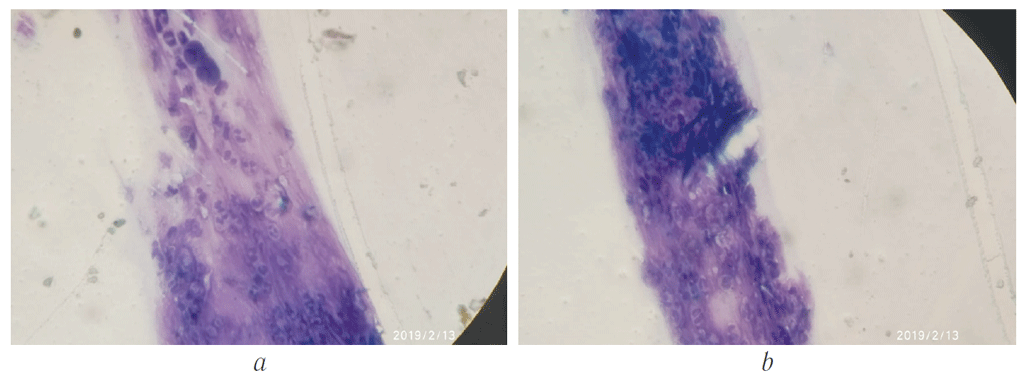

By postoperative Days 5–7, positive changes in cytograms were registered mostly in patients of the main group. They were characterized by a significantly lower content of NL, MF, and LC, indicating a more rapid subsidence of the inflammatory process compared with patients in the control group (p < 0.05) (Fig. 1).

Fig. 1. Cytological scraping from wound surface of surgical area on 5–7th postoperative day: а – the main group; b – the control group

Рис. 1. Цитологический соскоб с раневого края оперированной зоны на 5–7-е послеоперационные сутки: а — основная группа, b — контрольная группа

By postoperative Days 10–14, all patients in the main group demonstrated a significant decrease in the cytological signs of inflammation in scraping smears. At the same time, MF, LC, and FB were found in cytograms in the control group, and indicated incomplete resolution of inflammatory process and noncompletion of reparative reactions.